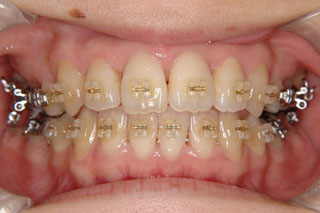

主訴:前歯の歯並び

診断名:開咬傾向を伴う叢生

年齢:31歳

使用した主な装置名:マルチブラケット装置

抜歯/非抜歯および抜歯部位:抜歯(上顎左右第一小臼歯、下顎左右第二小臼歯)

治療期間:動的処置2年6か月、経過観察3年

開咬と叢生が見られます。どうやら左右小臼歯間の歯は、それまでの人生でほとんど使われてこなかったようです。なので通常ですと、萌出してきたらほどなく消えてしまう前歯の先端のギザギザ(切縁結節)がそのまま残っています。概ねこのような開咬の場合は、前歯で噛もう噛もうとしているため、臼歯部を回転中心にした顎位のズレを生じている事が多いです。中心位マウントの咬合器やCPI測定で、更に大きな開咬である事が見つかります。

むりやり非抜歯で並べると、まるで前歯が噛まなくなったり、さらに顎をずらして噛む人になってしまいますので、小臼歯抜歯で対応しています。このケースでは下顎の非対称も見られるのですが、治療メカニクスが不十分であったため、正中変位の改善が達成されませんでした。しかし開咬傾向が強いケースでは、できるだけ顎間ゴムは使わない事にしています。なぜなら、そのようなメカニクスは多かれ少なかれ、顎関節のズレを生じさせると考えられるからです。今時分なら、歯科矯正用アンカースクリューのメカニクスを用いて改善しているでしょう。